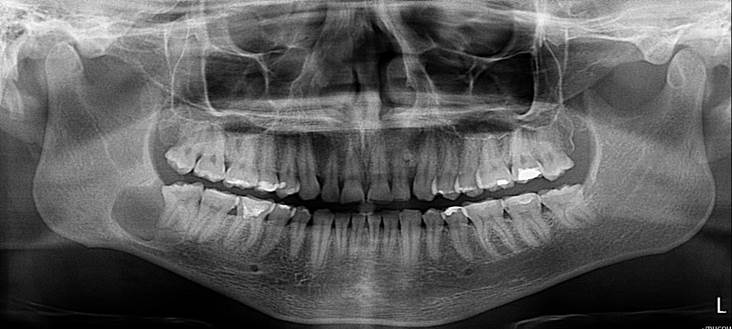

Figura. 1. Ortopantomografía inicial, hallazgo ocasional. Fuente Palima (2016).

Componente hipodenso, con destrucción de la cortical superior de la hemimandibula derecha, ubicado en la Ud. 48, quedando las raíces del mismo sumadas a la lesión, tiene un diámetro de 2.5 x 2.2 x 1.3 cm y densidad del tejido solido de 66UH. Se plantea TU óseo  primario de hemimandibula, sin embargo no se descarta proceso infeccioso de tipo absceso de evolución crónica, y afectación del canal mandibular, asociado a la lesión.

Sse procede a evaluar y analizar ortopantomografia inicial, lo cual hace referencia a una lesion de 1,7 cm x 2cm aproximadamente ya que esto es referencial, evaluación de imágenes de TAC,  analisis de informe imagienológico,       exámenes     de laboratorio que arrojan leve aumento de la serie blanca asociada a infección, ya con todos estos datos clinicos e imagienológicos, se  procede a la discusión y planificacion quirúrgica en la que se decide su remocion  completa y no parcial, realizar estudio histopatológico esperando los resultados bajo conducta espectante si amerita un segundo tiempo quirúrgico.

Figura 4.  Ortopantomografia con medidas estimadas del tamaño de la lesión. Fuente Palima (2016).